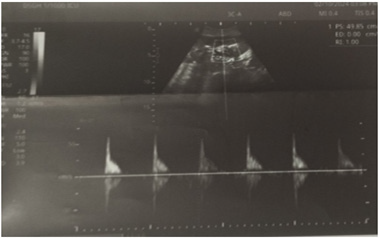

Figure 2: Distended bladder having 20-weeks-sized pregnancy due to blood clot obstruction at urethra (examination was done from left side as patient’s right side was stuck with drip stand).

Liver enzymes continued to rise; ALT was 86 U/L; AST was 384.4 U/L; and, alkaline phosphatase was 256.2 U/L. Hematuria was massive amounting to hypovolemic shock; therefore, the patient was resuscitated with fluids and fresh blood. Figure 5-6 show hematuria in tube of indwelling urinary catheter, urinary bag and urine bottles. A total of 13 units of blood and blood products were transfused. Ultrasonogram was repeated; there were echogenic contents and septation in the urinary bladder; uterus was normal. The allograft kidney was 11X 5.X 6.6cm and cortical thickness was 9.7mm; it showed increased cortical echogenicity; corticomedullary junctions were preserved; echogenic foci with posterior shadowing were observed in the calyces; Resistive Indices (RI) became elevated (main renal artery was 0.87; segmental artery was 1.0; interlobar artery was 1.0). Native kidneys showed bilateral nephropathy with upper pole renal cyst in right kidney. Figure 7-8 demonstrate ultrasonographic findings.

Figure 7: Allograft kidney with increased cortical echoes and echogenic foci with posterior shadowing in the calyces.